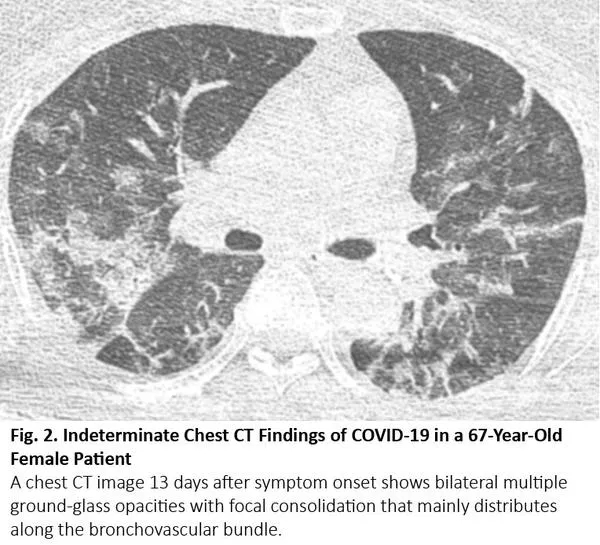

肺癌CT通常表现为结节或肿块,但有时也可表现为空洞。浸润性黏液腺癌是一个著名的例子,可呈现实性病变,伴或不伴磨玻璃样影,类似肺炎。腺癌的特定亚型,包括伏壁式、腺泡型和乳头型为主的腺癌,CT图像可呈现毛玻璃样阴影的区域。16当这些病变发生在肺部多处,其胸部CT可能与COVID-19有相似(图6)。如果既往的胸部CT显示这些病变已经持续存在,则可以与COVID-19区分。

图6. 一位66岁粘液性肺腺癌患者肿瘤复发后的胸部CT